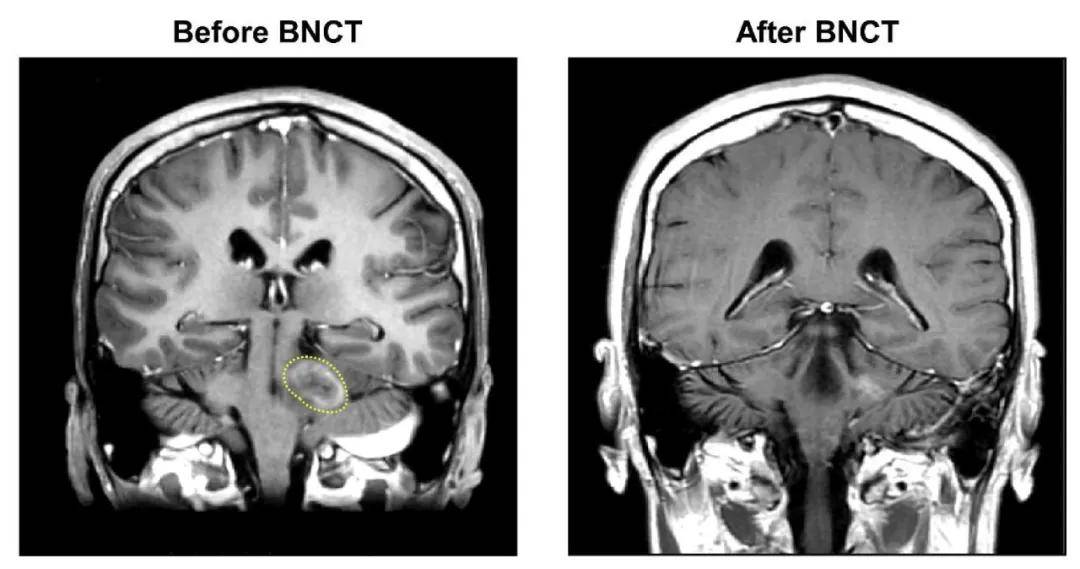

硼中子俘获疗法是几十年前提出的一种创新的放射治疗方法。该方法首先为患者注射含硼药物,这类药物和癌细胞有很强的亲和力,并很快聚集在肿瘤细胞内,而很少在正常组织中聚集。然后对患者的肿瘤部位进行热中子照射。当热中子被肿瘤细胞中的硼-10同位素俘获时发生裂变,可以杀死肿瘤细胞。

京都大学日前发布新闻公报说,硼中子俘获疗法能有效治疗以往难以治疗的复发性癌症和浸润性癌症。目前临床上多使用4-硼-L-苯丙氨酸(L-BPA)作为硼中子俘获疗法中的硼载体。但在部分癌症中,L-BPA不仅进入癌细胞,也能进入周围的正常细胞。如果用热中子照射,硼元素也可能导致正常细胞受损。所以,根据发生部位不同,有的癌症能用硼中子俘获疗法,有的则不能。

与L-BPA相比,4-硼-D-苯丙氨酸(D-BPA)很难向癌细胞聚集,所以一直被认为是“无用”的化合物。京都大学和东京大学等机构的研究人员发现,液体胶水成分——聚乙烯醇(PVA)在与D-BPA结合后形成的化合物PVA-D-BPA向癌细胞的选择性聚集能力会大大提升。动物实验显示,使用PVA-D-BPA作为硼载体的硼中子俘获疗法能使小鼠的皮肤肿瘤基本消失。